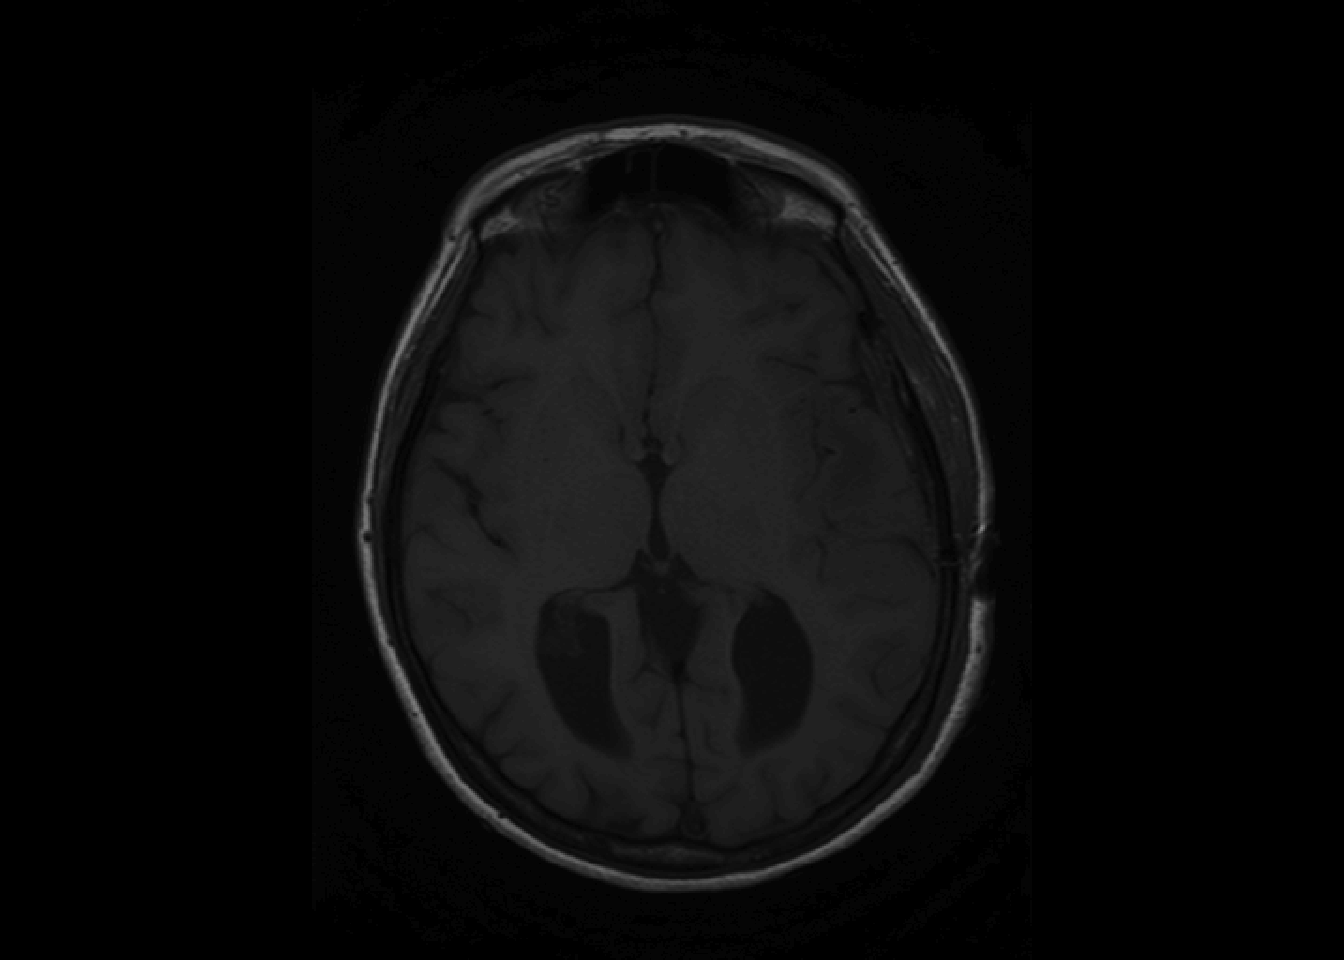

However, oro.nifti has its own image function which is called by default one NIfTI objects.

If no arguments are passed for coordinates, oro.nifti::image plots all the slices axially.

The orthographic functions allows to visualize a single point from three dimensions.